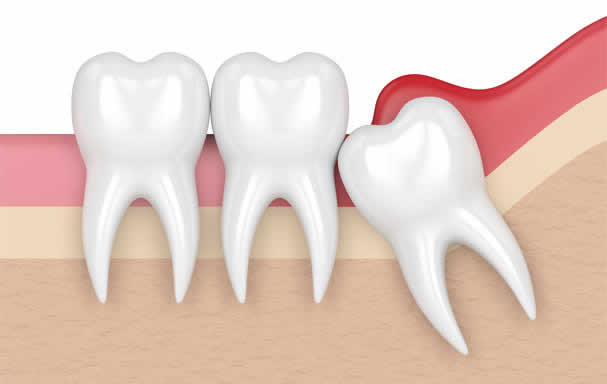

Gömülü diş çıkma zamanı geldiği halde çene kemiği içinde kalan ve normal konumunu alamayan dişlere verilen isimdir. Dişler ağızda kemik dokusu ve dişeti dokusu tarafından çevrelenir. Dişler ağızdaki yerlerini alırken önce kemik dokusunu geçer daha sonra dişeti dokusunu geçer. Bazı dişler bu iki dokuyu birden ya da sadece dişetini geçemez ve ağız içerisine tam olarak ulaşamaz.

Yirmi yaş dişleri genellikle çene kemiği içerişindeki konumu , üzerinin dişeti veya kemikle kaplı olmasından dolayı gömük durumundadır. Dişin bir bölümü dişeti ile kaplı olduğu durumlarda sıklıkla enfeksiyon ve buna bağlı olarak yüzde şişme ve çene açmada azalma meydana gelir.